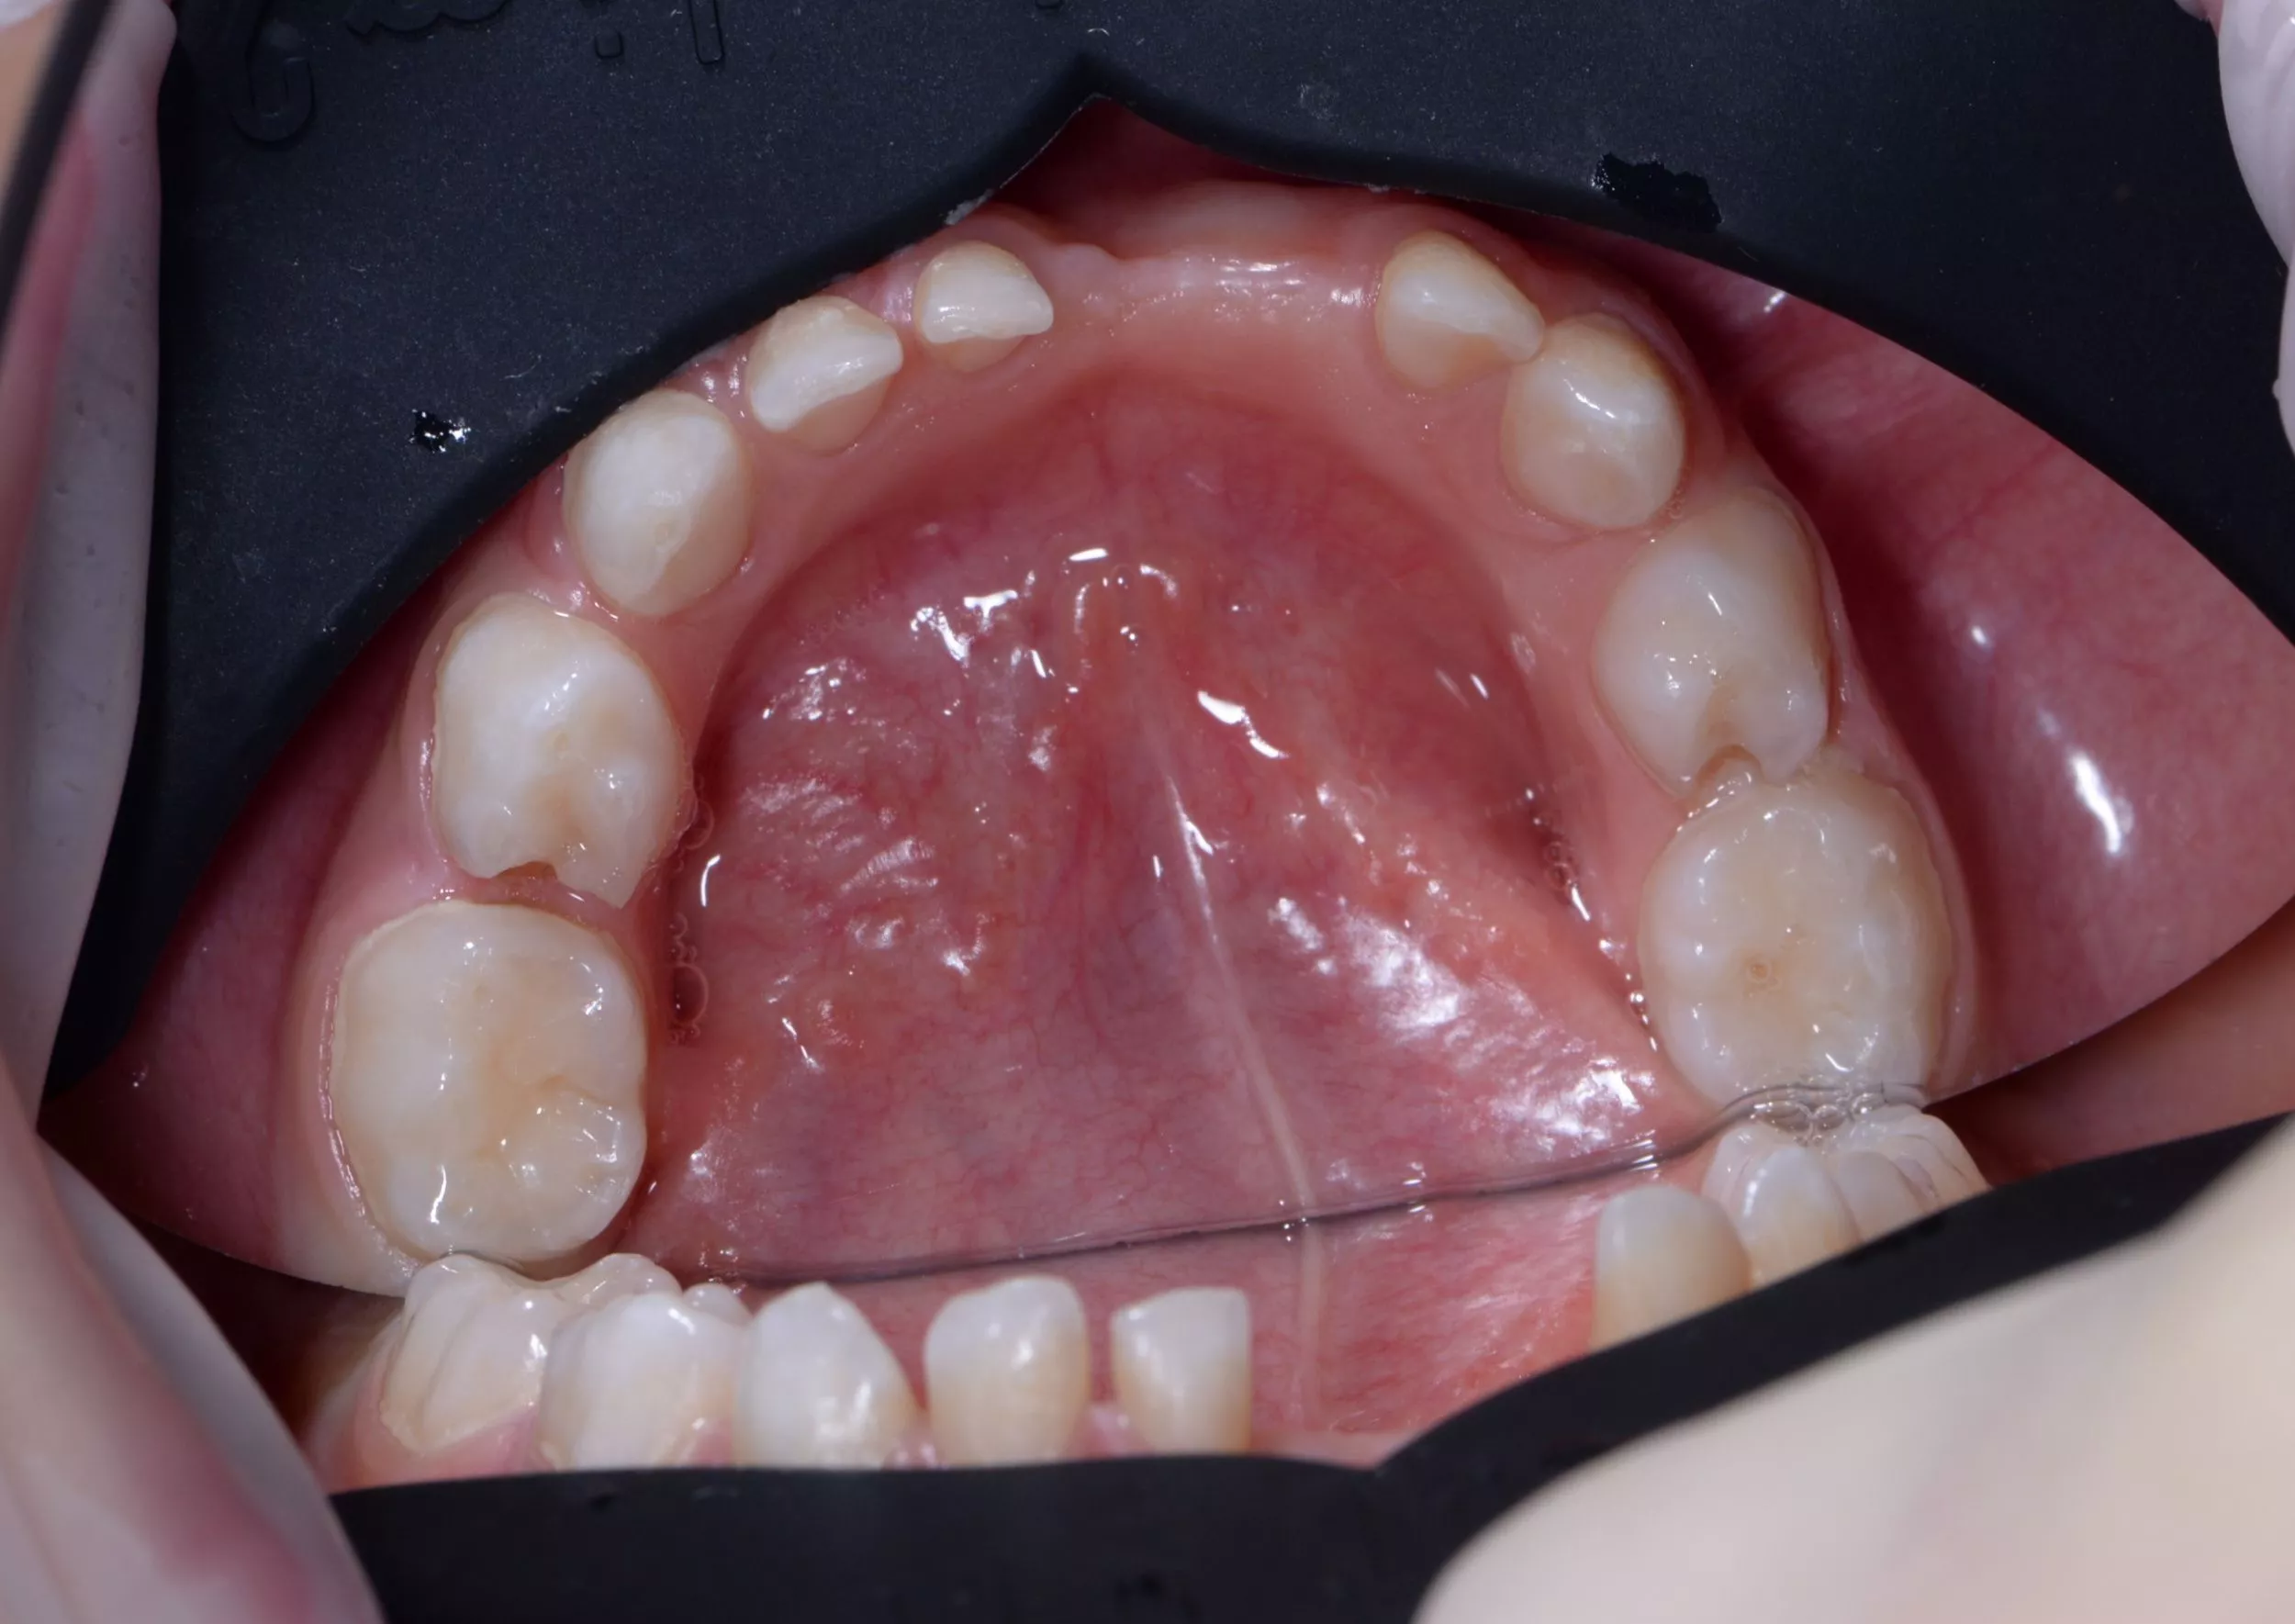

После